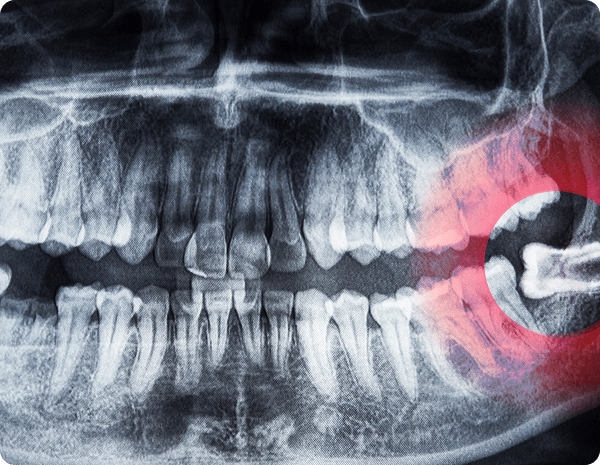

Les dents de sagesse sont fréquemment concernées par des inclusions osseuses ou des poussées douloureuses.

Nous réalisons leur extraction de manière sécurisée

et planifiée, notamment si elles provoquent :

L’intervention peut nécessiter une incision gingivale et une désinclusion osseuse partielle ou complète, sous anesthésie locale.